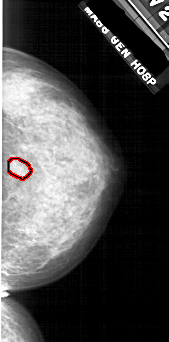

A_1808_1.LEFT_MLO

LEFT_MLO LINES 5101 PIXELS_PER_LINE 2251 BITS_PER_PIXEL 12 RESOLUTION 43.5 NON_OVERLAY

FILE: A_1808_1.RIGHT_MLO.OVERLAY

TOTAL_ABNORMALITIES 1

ABNORMALITY 1

LESION_TYPE MASS SHAPE IRREGULAR MARGINS ILL_DEFINED

ASSESSMENT 4

SUBTLETY 2

PATHOLOGY BENIGN

TOTAL_OUTLINES 1

BOUNDARY